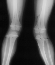

X-Ray Set 4. 3 Months post Surgery , Left 6* Mechanical axis

X-Ray Set 5. 9 Months post Surgery Left 10* Mechanical axis